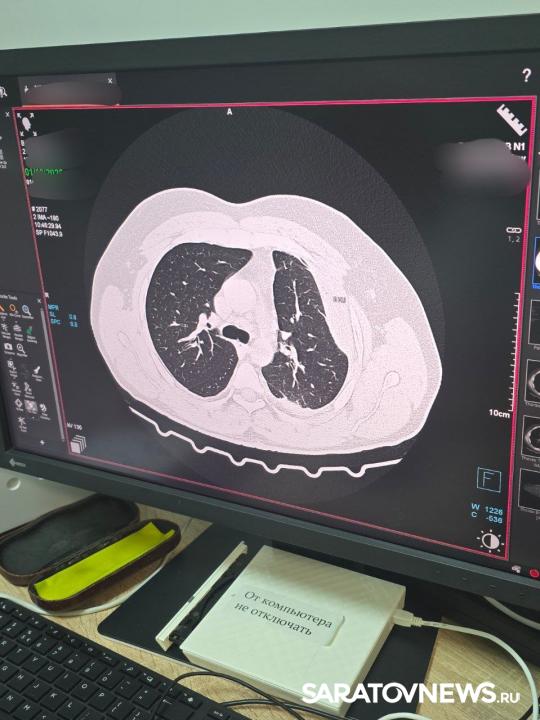

Больница с широким профилем оказания медицинской помощи оказывает помощь жителям не только Энгельса, но и 12 левобережных районов, включая отдаленные. Сейчас здесь работают два компьютерных томографа, и очередь на этот вид исследования ликвидирована.

В рамках реализации программы модернизации первичного звена здравоохранения нацпроекта «Здравоохранение», инициированного Президентом РФ Владимиром Путиным приобретен компьютерный томограф SOMATOM go.Now.

«Оборудование делает качественную медицинскую помощь более доступной, в приборе реализованы инновационные разработки в области организации рабочих процессов и удобства использования, которые повышают эффективность исследования. Все это обеспечивает замечательные результаты диагностики», - рассказал корреспонденту «Saratovnews» главный врач больницы Аслан Юанов.